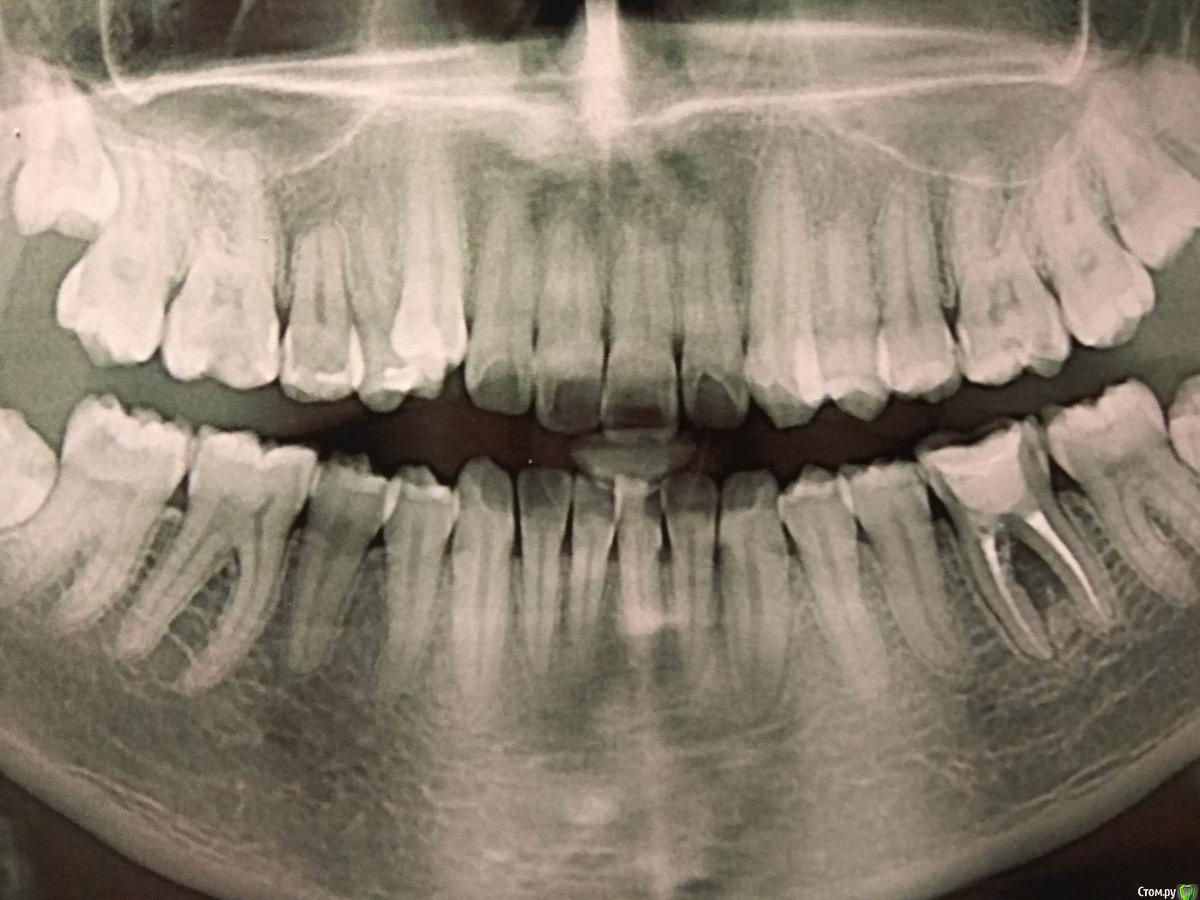

Paganini Опубликовано 20 ноября, 2017 Поделиться Опубликовано 20 ноября, 2017 Приветствую!Раз уж форум создан для общения, получения знаний и советов, то прошу помочь с клиническим случаем.Как я понимаю, в области 36 зуба была перфорация, за которой последовало разрежение костной ткани в области бифуркации, плюс есть расширение периодонтальной щели и прочее... Лечение - удаление.Вопрос: есть ли варианты консервативного лечения, которые дадут положительный результат? Три врача сказали удалять, но я читала, что можно попробовать использовать Pro-poot в области перфорационного отверстия. Или может Каласепт? Или есть еще какие-либо варианты?Реально? Да/нет? Кто пробовал? Или оно того не стоит?:P.S.: что касается этого зуба, то жалоб у пациента нет. Ссылка на комментарий

vse32 Опубликовано 21 ноября, 2017 Поделиться Опубликовано 21 ноября, 2017 почему бы не попробовать зуб сохранить? Простите, а что значит сохранить. Оставить как есть? С резорбцией в бифуркации и ждать свищей? Перфорация там есть, ее даже видно. Это не пропущенная анатомия в бифуркации. Там в районе устья медиального корня какая-то каша. И что в таком случае сохранять? Кисту?Практика показывает, что такие зубы почти всегда оканчивают свой жизненный цикл под щипцами. Это только в начале кажется, что ты супергерой. А с опытом понимаешь, что некоторые обстоятельства не подвластны твоим возможностям. 2 Ссылка на комментарий

parallax Опубликовано 24 ноября, 2017 Поделиться Опубликовано 24 ноября, 2017 Народ, а где перфорация? Резорбция да, есть, но свод бифуркации целый. Ссылка на комментарий

makinos Опубликовано 24 ноября, 2017 Поделиться Опубликовано 24 ноября, 2017 Свод целый, а в районе устьев медиального корня насверлено-намазано 1 Ссылка на комментарий

parallax Опубликовано 25 ноября, 2017 Поделиться Опубликовано 25 ноября, 2017 Не было тут перфорации, устья запакованы равномерно. А у резорбции другая причина. Ссылка на комментарий

Л Ю С Я Опубликовано 25 ноября, 2017 Поделиться Опубликовано 25 ноября, 2017 Народ, а где перфорация? Резорбция да, есть, но свод бифуркации целый.Смотрите на устье мед каналов. Вообще без кт в таких случаях больше догадки Ссылка на комментарий

parallax Опубликовано 25 ноября, 2017 Поделиться Опубликовано 25 ноября, 2017 Смотрите на устье мед каналов. Вообще без кт в таких случаях больше догадки Была бы перфора, силер был бы в этой перфоре. А так медиальные каналы запломбированы в идеальном конусе. Да и следов закрытия перфорации не наблюдается (тот кто лечил зуб 5 лет назад не совсем же дебил, чтобы оставить перфорацию незакрытой).А так да, нужно делать КТ. Ссылка на комментарий

parallax Опубликовано 25 ноября, 2017 Поделиться Опубликовано 25 ноября, 2017 Совсем не обязательно , что там должен быть силер.Самое лучшее композит. В худшем случае вонючка))) Но там нет ни композита, ни СИЦа, ни силера, ни перфорации. Только резорбция (ХЗ, может уже и вонючка). Ссылка на комментарий

Л Ю С Я Опубликовано 25 ноября, 2017 Поделиться Опубликовано 25 ноября, 2017 В принципе не важно : резорбция , перфорация. Однозначно, есть нарушение целостности стенки корня и микробы 2 Ссылка на комментарий

vse32 Опубликовано 25 ноября, 2017 Поделиться Опубликовано 25 ноября, 2017 Но там нет ни композита, ни СИЦа, ни силера, Откуда такая уверенность? Есть куча не рентгенконтастных материалов. Те же МТА и аналоги, кальций, композиты (Градия например) не контрастны. Все это в вонючем виде там может находиться. Ставлю на МТА и аналоги или кальций. Ссылка на комментарий

parallax Опубликовано 25 ноября, 2017 Поделиться Опубликовано 25 ноября, 2017 Вообще-то, оксид висмута рентгеноконтрастен. И покажите мне идиота, который будет закрывать перфорейшн Градией? То же касается кальция. Ставлю на то, что там нет перфоры. Там другая проблема, из-за которой и получилась резорбция и из-за которой зуб подлежит удалению. Ссылка на комментарий